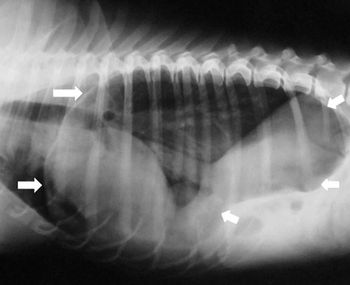

This case report describes the clinical signs and surgical treatment of an unusual hiatal hernia in a Chinese Shar-Pei.